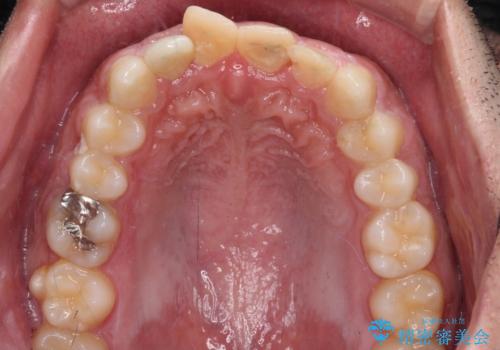

- 酒席の後に転倒して前歯を損傷し、応急処置のみを受けてきたとのことで来院された患者様です。

損傷がひどく、前歯4本と広範囲であったため、症状やレントゲン写真、検査結果が一致せず、定期的に経過を見ながら診断していくこととしました。

右側前歯は歯根が短くなり、パンチング状に歯根に透過像が認められたため、予後不良と判断し抜歯することとしました。

当初のレントゲン写真では根尖部に骨透過像が認められた両サイドの2歯は、歯髄の正常な反応が認められたためそのまま保存し、左側前歯は歯髄が失活していたため根管治療を行うこととしました。

抜歯後の欠損部はブリッジにて補綴治療を行うこととしました。

事故直後のレントゲン写真では全ての歯の根尖部に骨透過像が認められましたが、治療後には全ての透過像がなくなっていました。